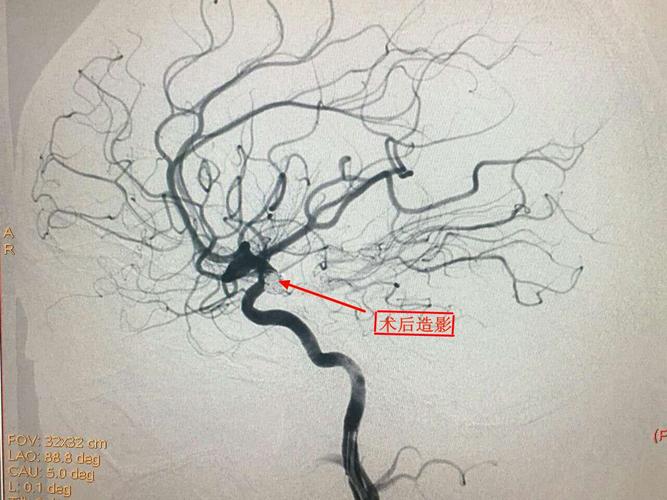

脑血管造影术

脑血管造影术,脑血管支架手术过程

"小"手术"大"疗效 航天城院区成功开展全脑血管造影术

全脑血管造影术护理ppt

我院成功实施首例全脑血管造影动脉瘤栓塞手术

全脑血管造影术简介

我院成功开展首例经桡动脉全脑血管造影术

全脑血管造影术图片

脑血管造影图片